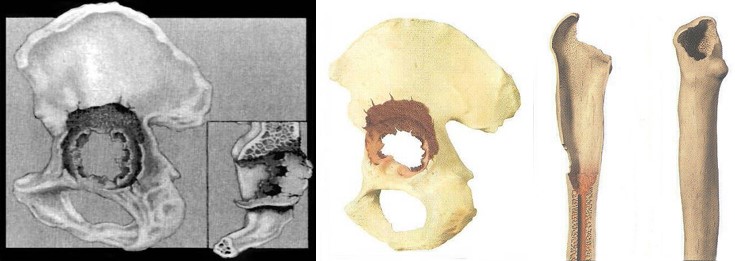

Приклад заміщення дефектів кісток тазу при ураженні пухлиною. Складне індивідуальне ендопротезування кульшового суглоба

Найважливішою з проблем ревізійного протезування є наявність у хворих дефектів кісткового ложе протеза, як результат гранулематозного запалення, що виникає під дією продуктів зношення та руйнування пари тертя.

Окремо стоїть проблема ендопротезування онкологічних хворих після великих резекцій кісткової тканини та дефекти військового часу.

В своїй роботі ми класифікацією кісткових дефектів ложе нестабільнокористувалисяго протеза колінного суглоба за AORI (Anderson Orthopaedic Research Institute, USA), 1997 де автори виділяють 3 типа кісткових дефектів

Тип 1 – інтактна кістка (intact metaphysealbone) – невеликі кісткові дефекти, зазвичай без пошкодження кортикальної кістки. Характеризується нормальною кісткової структурою і збереженням губчастої і кортикальної кістки метафиза, нормальним рівнем суглобової лінії. позначаються як F1 – для стегнової кістки і Т1 – для великогомілкової.

Тип 2 – пошкоджена кістка (damаged metaphyseal bone) – характеризується втратою губчастої і кортикальної кісткової маси метаепіфізів, без заповнення якої неможливе створення надійної опори для компонентів ревізійного імплантату і відновлення анатомічного рівня суглобової лінії. (F2 А та F2 Б – для стегнової і Т2 А та Т2 Б – для великогомілкової кісток)

Тип 3 – дефіцит кістки (deficient metaphyseal segment) – характеризується вираженою втратою губчастої і кортикальної кісткової маси метаепіфіза, без компенсації якої неможливе створення опори для компонентів ревізіційного імплантату і відновлення нормального рівня суглобової лінії. Дефекти частіше поширюються до надвиростків і вище на стегнової кістці або до горбистості і нижче на великогомілковій кістці. (F3 А та F3 Б – для стегнової і Т3 А та Т3 Б– для великогомілкової кісток)